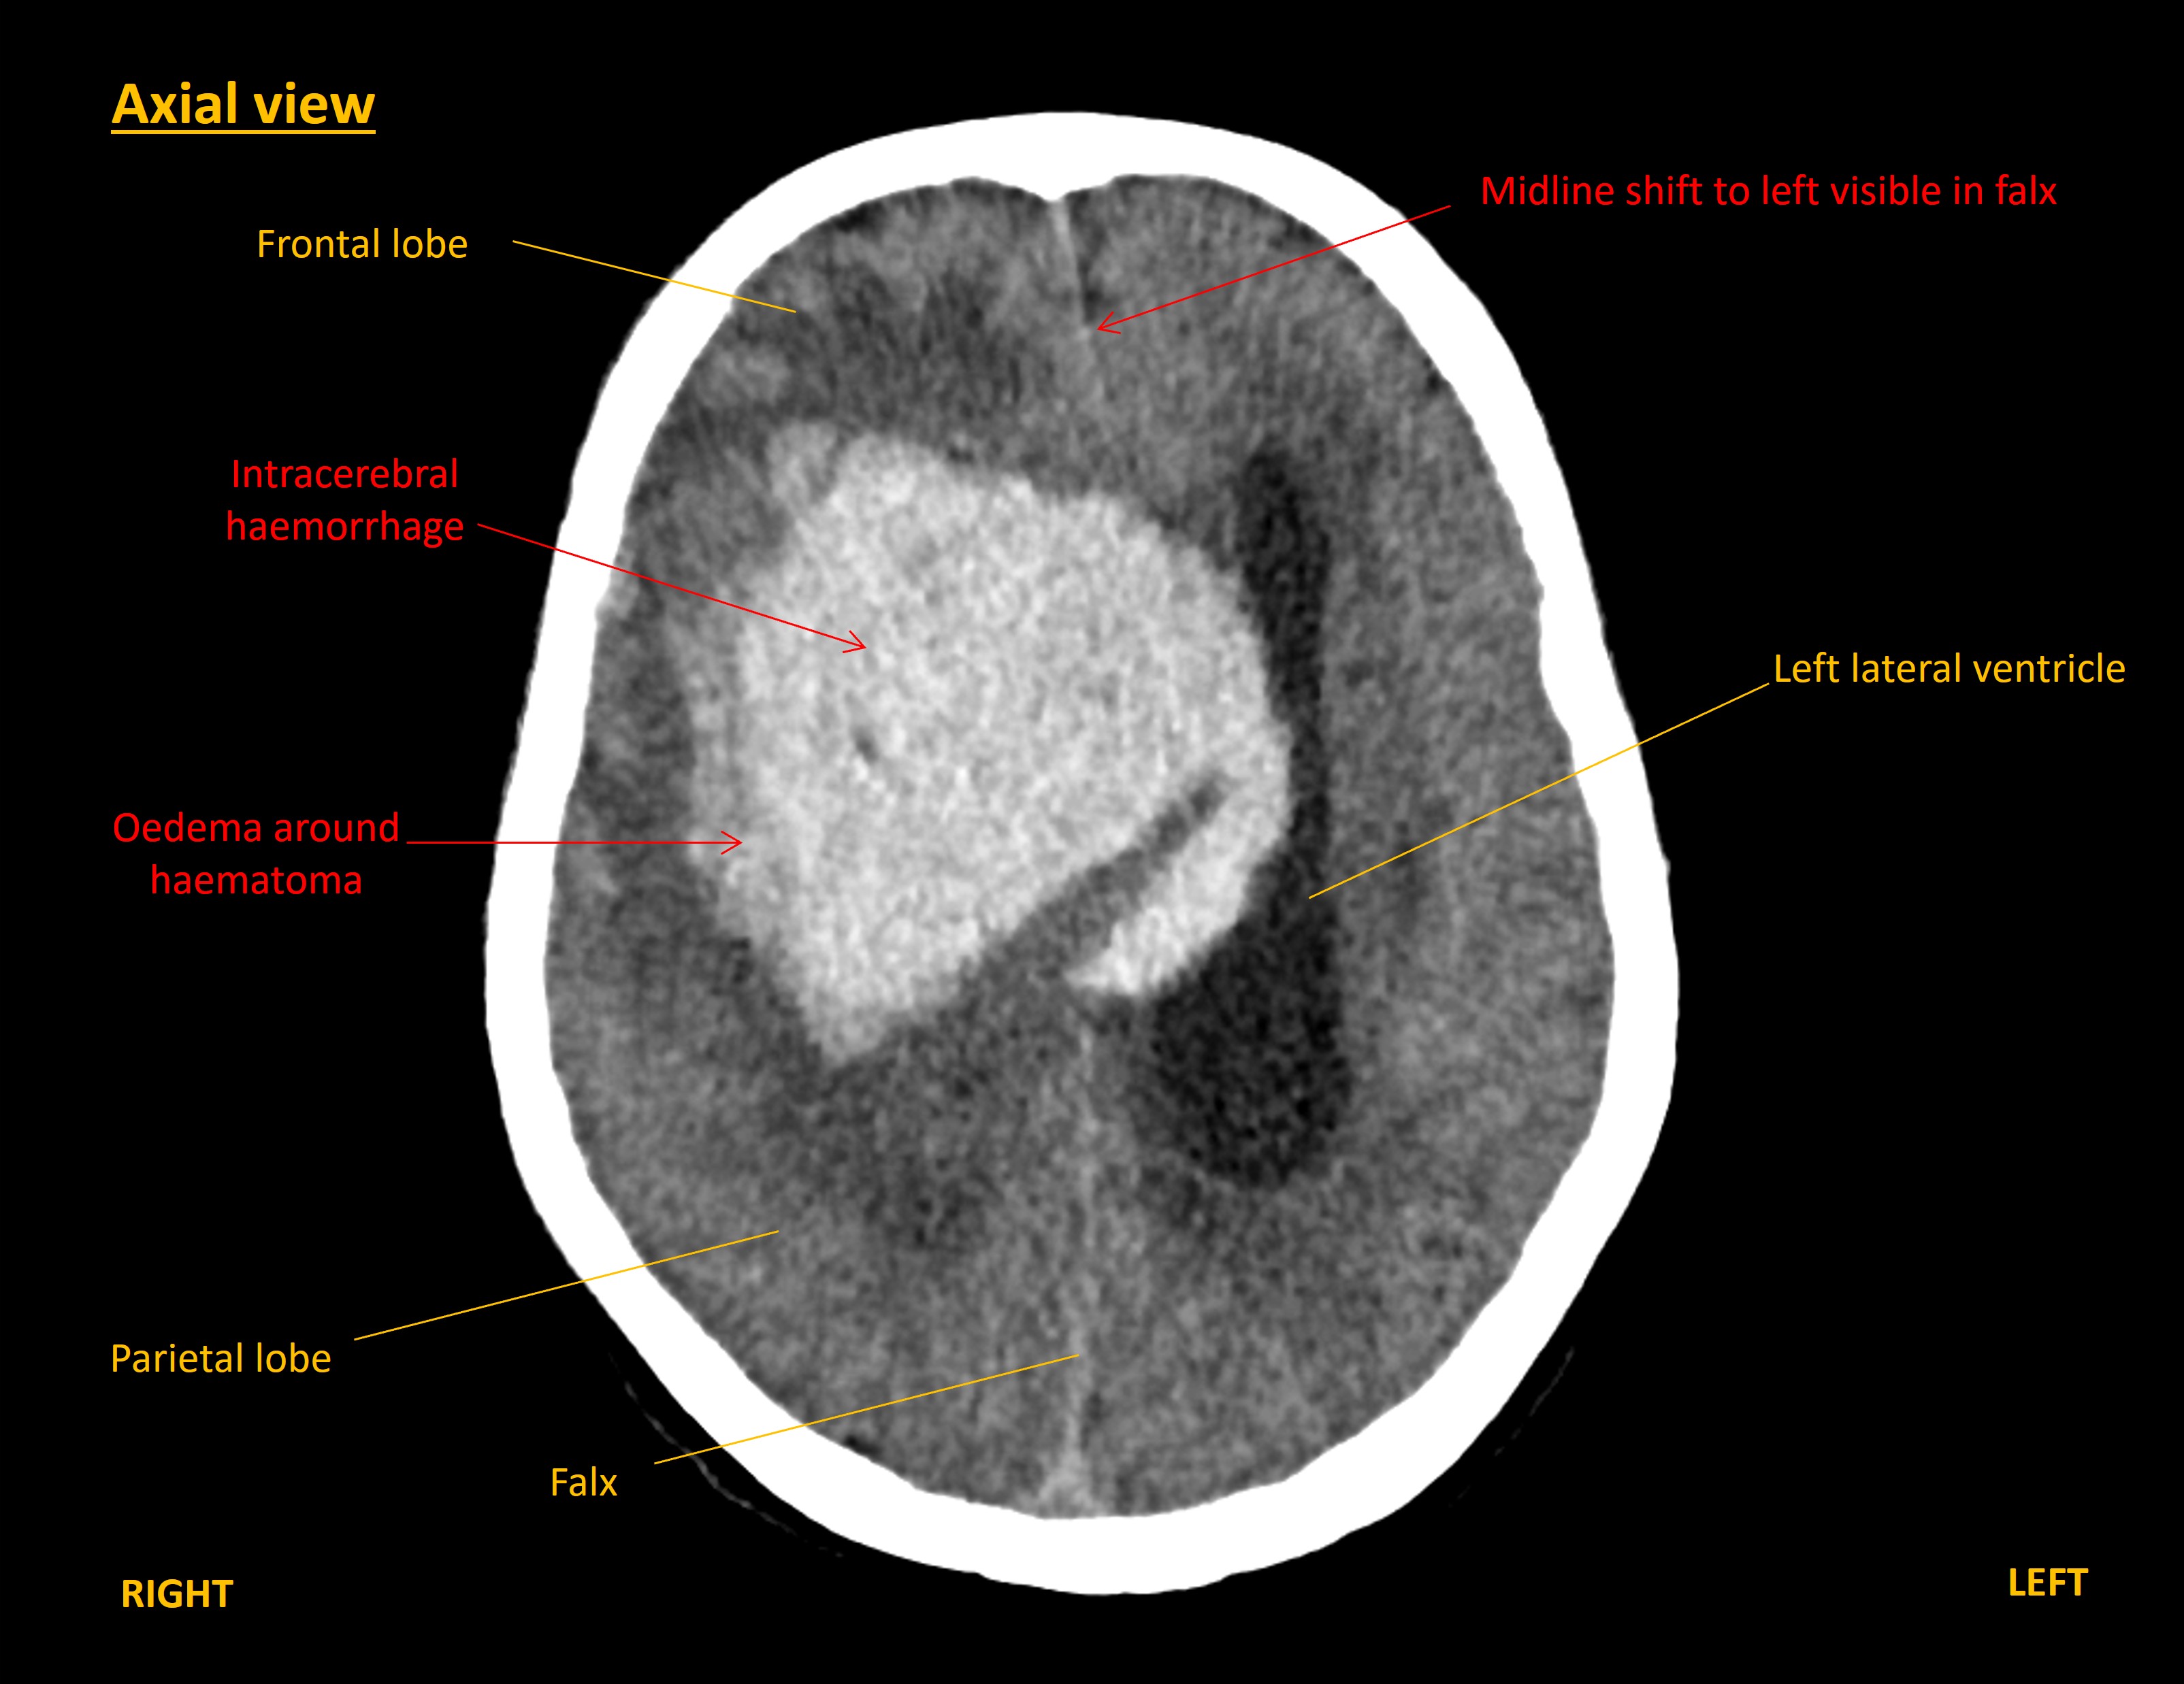

A CT brain was performed immediately. This showed a large right-sided intracerebral haemorrhage within the frontal and parietal lobes. The blood was causing mass effect with midline shift towards the left, and right uncal herniation. The haemorrhage had extended into the ventricles, including down to the fourth ventricle, with hydrocephalus.